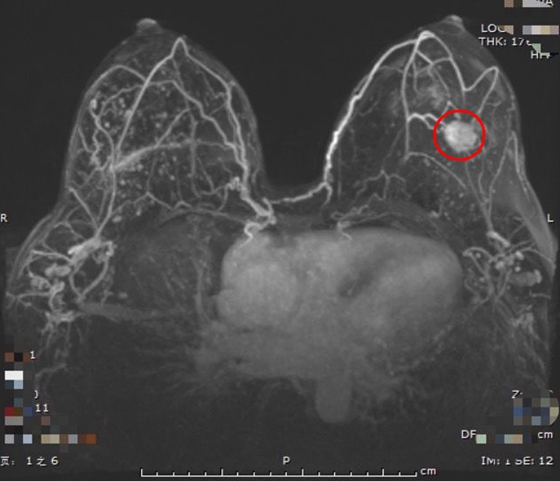

经普外科孙道副主任医师接治,综合分析了患者的需求及病例资料。王女士为左乳浸润性癌,左乳肿物仅2厘米大小,距离乳头约4厘米,腋窝淋巴结临床阴性,且胸腹部增强CT未见远处转移,乳腺MRI未见多中心性、多灶性病变,加之其双乳丰满,有强烈的保乳意愿,孙道认为可行乳腺癌保乳术。